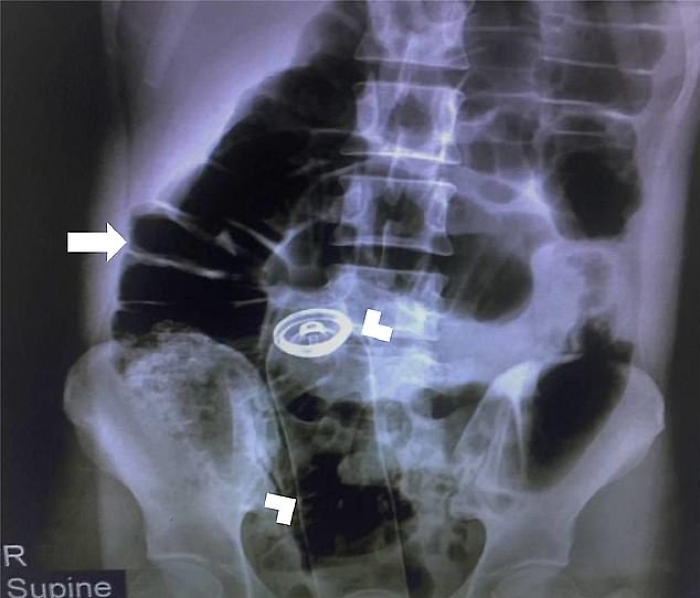

deodorant-rectum-x-ray

Un gioco erotico finito male, molto male. Un uomo ha rischiato di morire e ha dovuto essere sottoposto ad un intervento chirurgico d'urgenza, dopo che una flacone di deodorante è rimasto incastrato nel retto. L’uomo, un trentenne, ha richiesto assistenza medica "due ore dopo aver inserito un contenitore di deodorante nel suo retto", secondo quanto è stato pubblicato sul Visual Journal of Emergency Surgery.

Il paziente di nazionalità iraniana si era presentato al pronto soccorso per un "dolore addominale acuto". I raggi X hanno poi rivelato le cause. I chirurghi gli hanno praticato un'incisione sullo stomaco e gli hanno rimosso il flacone. Il paziente ha trascorso un giorno sotto osservazione prima di essere dimesso dall'ospedale.